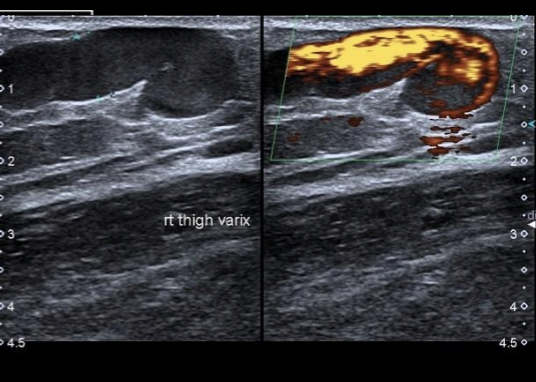

10

Q

A

TVO vena subsartorial